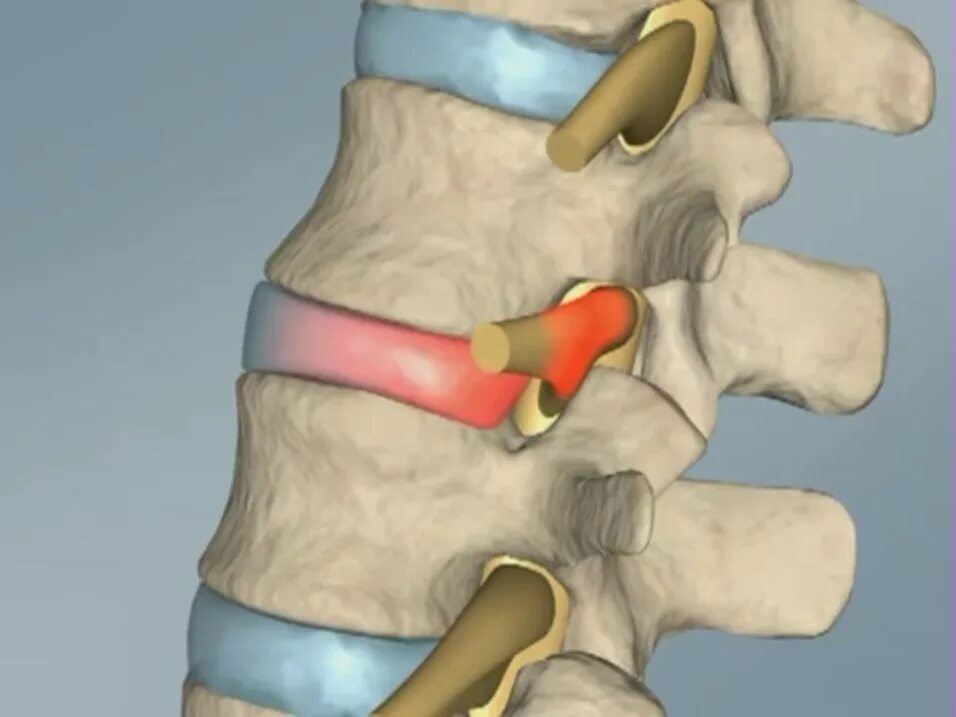

Спондилоартроз l4 s1 сегментов